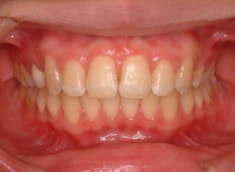

治療後(1年9ヶ月後)